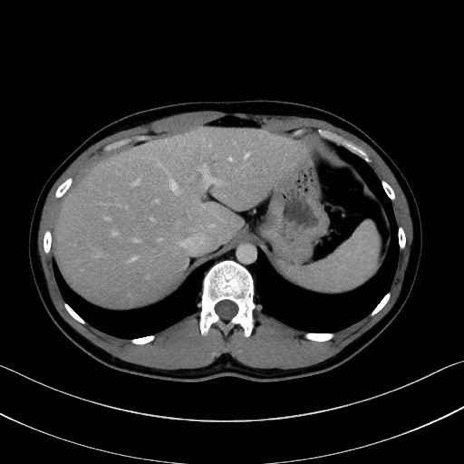

腹直筋 (Rectus abdominis)

外腹斜筋 (External oblique)

内腹斜筋 (Internal oblique)

腹横筋 (Transversus abdominis)

広背筋 (Latissimus dorsi)